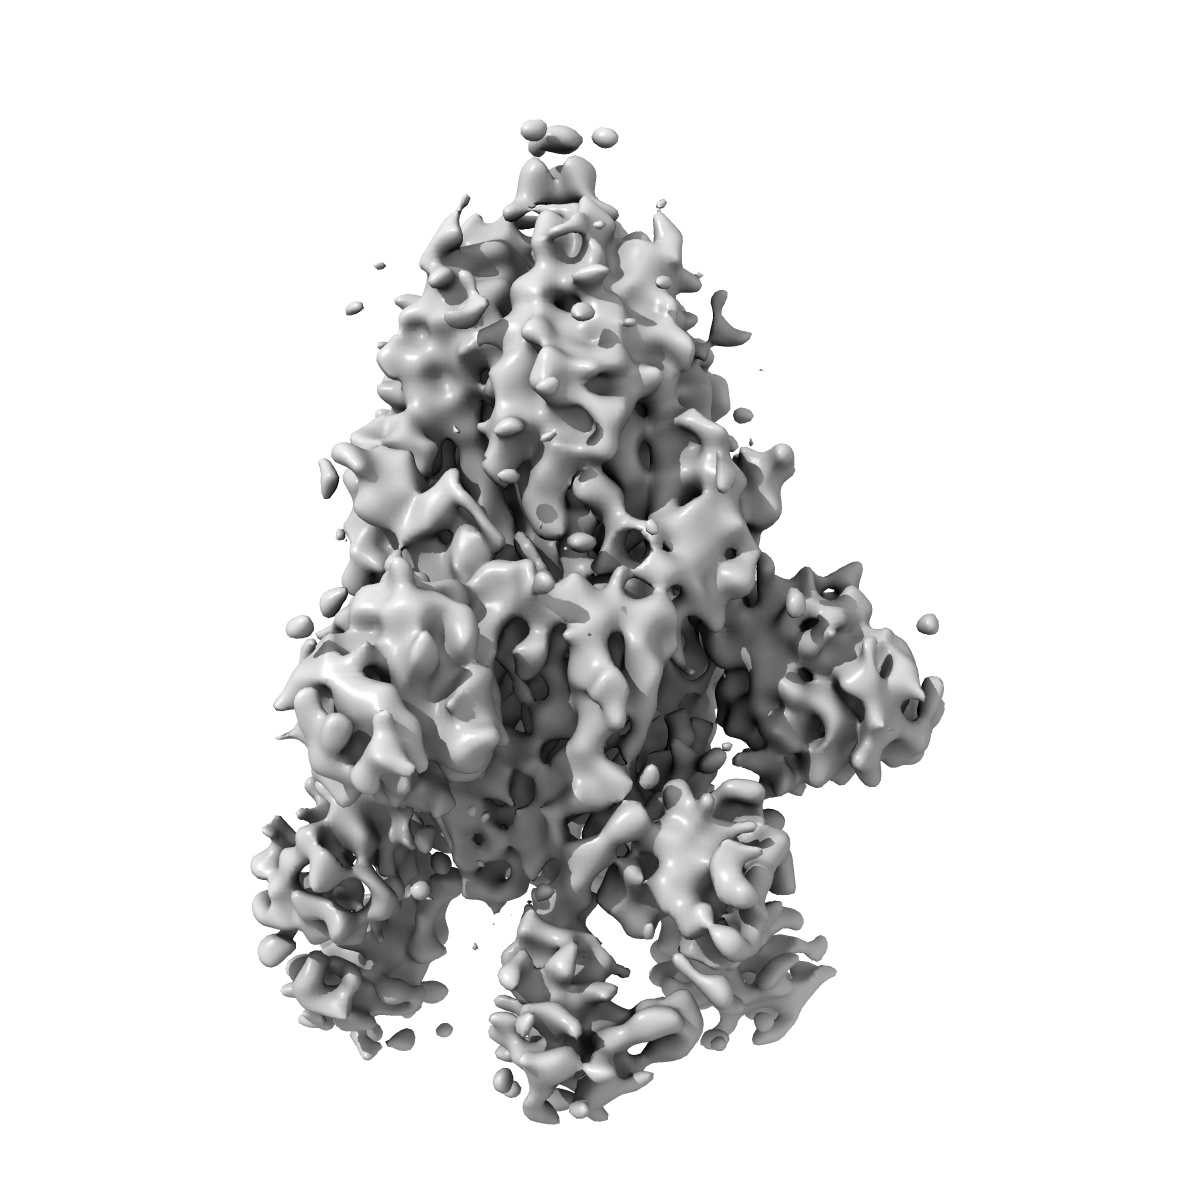

EMD-24895

Ab20 in complex with SARS-CoV-2 spike (6P)

Single-particle9.2 Å

Sample: Ab16 Fab in complex with SARS-CoV-2 Spike (6P)